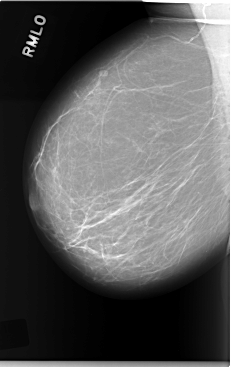

C_0042_1.RIGHT_MLO

RIGHT_CC LINES 5848 PIXELS_PER_LINE 3600 BITS_PER_PIXEL 12 RESOLUTION 50 NON_OVERLAY

RIGHT_MLO LINES 5864 PIXELS_PER_LINE 3688 BITS_PER_PIXEL 12 RESOLUTION 50 NON_OVERLAY